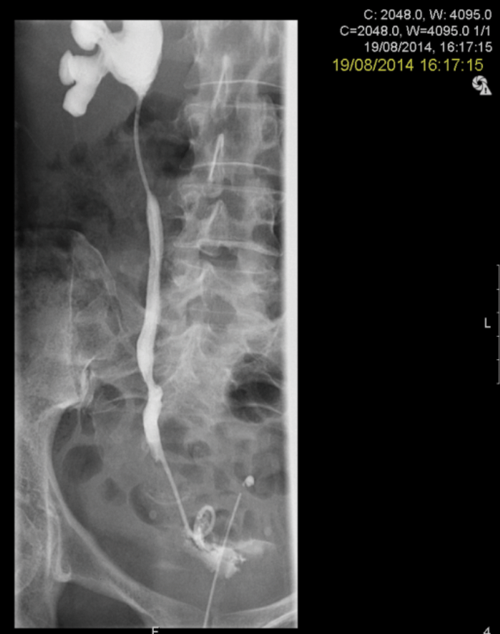

3a. Right antegrade wire insertion and pull-through.

3b. Right JJ stent in situ. Failed left antegrade wire passage.

3c. Left intraoperative nephrostogram showing obliterated left distal ureter.

3d. Right nephrostogram one week postoperative.

Figure 3: A 51-year-old woman, initially presenting with acute kidney injury, with bilateral distal ureteric obstruction secondary to locally advanced cervical cancer. Bilateral rendezvous, technically successful on right but failed on left secondary to ureterovaginal fistula.